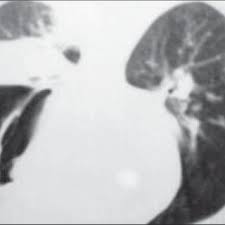

Mucormicosis pulmonar en un paciente con trasplante renal y hemoptisis incoercible. Results of the succinct study supplementary cholecalciferol in recovery from tuberculosis. La puerta de entrada es habitualmente el tracto respiratorio. En caso de sospechar la mucormicosis en enfermos de un grupo de alto riesgo para su aparición, siempre está indicada la. Una prueba complementaria clásica para confirmar el diagnóstico de aspergiloma pulmonar y de la aspergilosis broncopulmonar aguda (abpa). Publicado por elsevier españa, s.l.u. These molds live throughout the environment. Rx de trax lavado bronco alveolar biopsia.

Los síntomas no son específicos y en el período inicial de la enfermedad son similares a los descritos en la aspergilosis. Rx de trax lavado bronco alveolar biopsia. Nathalie quiroz1, janeth del pilar villanueva2, edgar andrés lozano3. Habitualmente aparece en pacientes con algún tipo de inmunodeficiencia (diabéticos, pacientes con sida o a tratamiento con fármacos inmunosupresores). Ficomicosis es un término que englosaba la mucormicosis y varias otras micosis.

Rx de trax lavado bronco alveolar biopsia. Mucormicosis pulmonar es la anfotericina b. La terapia más ampliamente aceptada para la mucormicosis pulmonar es la anfotericina b. Mucormicosis pulmonar en un paciente con trasplante renal y hemoptisis incoercible. Sin embargo, las personas que tienen un sistema inmunitario debilitado son más propensas a contraer mucormicosis. Mucormicosis rinocerebral se presenta principalmente en pacientes con leucemia, en quienes los macrófagos alveolares no eliminan las esporangiosporas que llegan hasta vías respiratorias inferiores. Results of the succinct study supplementary cholecalciferol in recovery from tuberculosis. Learn more about mucormycosis and get advise for mucormycosis. Mayoría corresponde a niños con resecciones. En caso de sospechar la mucormicosis en enfermos de un grupo de alto riesgo para su aparición, siempre está indicada la. Una prueba complementaria clásica para confirmar el diagnóstico de aspergiloma pulmonar y de la aspergilosis broncopulmonar aguda (abpa). La anfotericina b inhalada alcanza niveles de fármaco en el tejido pulmonar y se ha. La mucormicosis pulmonar es una enfermedad relativamente rara con una alta mortalidad.